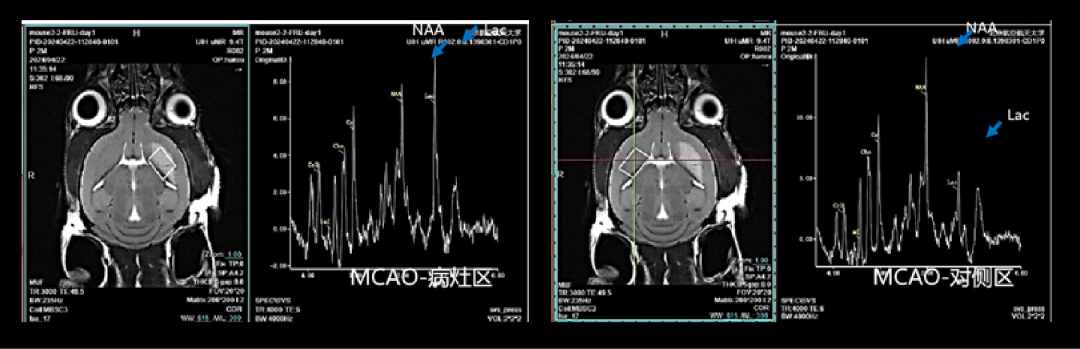

脑部磁共振波谱应用:

磁共振波谱成像,通过波谱图及数据,助力研究脑部代谢。例如脑卒中小鼠使用磁共振波谱成像,比较病灶区代谢物含量的变化(如图5),全方位为小动物脑科学研究提供影像支撑。

图5 小鼠脑部磁共振波谱成像